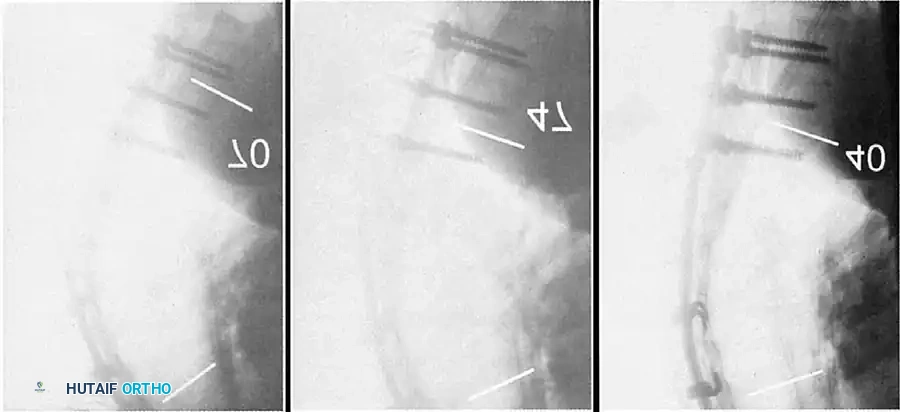

Lateral radiograph demonstrating classic Scheuermann kyphosis with severe anterior wedging and Schmorl nodes.

Preoperative lateral radiograph highlighting the rigid structural curve.

Detailed view of apical vertebral wedging and endplate destruction.

A lateral radiograph taken with the patient hyperextended over a bolster is critical to assess the flexibility of the curve and to aid in preoperative planning.

4. Rod Contouring and Reduction

Two rigid rods (typically 5.5mm or 6.0mm Cobalt Chrome or Titanium) are meticulously contoured. The rods must be under-contoured relative to the patient's current deformity but over-contoured relative to the desired final physiological kyphosis (aiming for 40 degrees).

Insertion of the contoured rod into the pedicle screw construct.

The reduction is achieved via a cantilever maneuver. The rods are seated in the distal foundation screws first. Using reduction tubes and set screws, the rod is sequentially drawn into the apical and proximal screws. This maneuver translates the spine to the rod, simultaneously correcting the kyphosis and restoring sagittal balance.

Cantilever reduction maneuver closing the posterior osteotomies and correcting the kyphotic deformity.